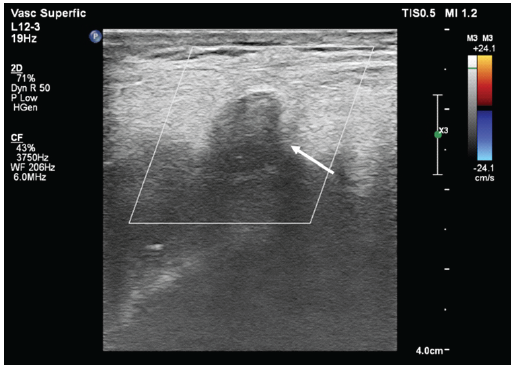

A 60-year-old male with a history of diabetes, hypertension, hypothyroidism, and coronary artery disease presented with acute painful swelling of the right knee. Clinical examination revealed diffuse swelling, tenderness over the knee joint and leg, and fullness in the popliteal fossa. Initial Doppler ultrasonography demonstrated a DVT of the right popliteal vein, and anticoagulation was initiated, leading to partial resolution of limb edema, although the knee swelling persisted. Subsequent magnetic resonance imaging (MRI) of the knee revealed a ruptured Baker’s cyst with a large joint effusion. Arthrocentesis yielded yellow, turbid synovial fluid, which cultured Staphylococcus aureus. The patient underwent arthroscopic lavage, Baker’s cyst decompression, and synovial biopsy. Histopathology and culture confirmed septic arthritis, and he was treated with intravenous culture-sensitive cephalosporin, resulting in symptomatic improvement and normalization of inflammatory markers. Three weeks later, the patient again presented with painful knee swelling. Aspiration at this stage revealed hemarthrosis, but cultures were sterile. The swelling decreased when anticoagulation was withheld, suggesting a possible anticoagulation-related bleed. However, a third episode of acute hemarthrosis occurred despite cessation of anticoagulation, raising suspicion of a vascular cause. Initial MRI of the knee demonstrated a periarticular lesion (Fig. 1), and Doppler ultrasonography suggested a vascular etiology (Fig. 2).

Figure 2: Doppler ultrasonography of the right knee demonstrating a well-defined periarticular vascular lesion with internal turbulent flow, consistent with a pseudoaneurysm (white arrow).

In this case, the pseudoaneurysm measured 10 × 8 mm with a narrow 2.7 mm neck, and Doppler demonstrated the classical “Yin-Yang” sign, confirming turbulent bidirectional flow and suitability for compression therapy. Magnetic resonance angiography subsequently confirmed a pseudoaneurysm arising from the superior medial genicular artery adjacent to the joint capsule (Fig. 3).